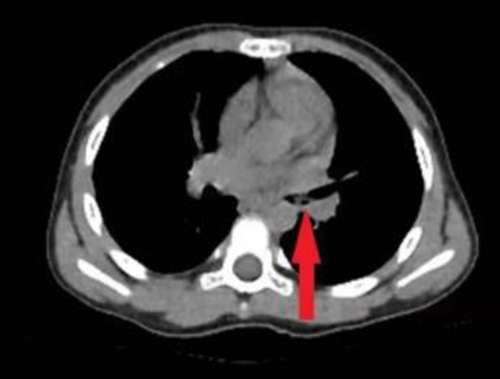

接診醫(yī)生詢問孩子病史,為其完善胸部CT、重建氣道,明確異物位置,發(fā)現(xiàn)小雨的左側(cè)支氣管內(nèi)有異物。